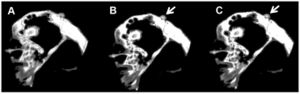

Publication: PLoS One. 2016 Jun 9;11(6):e0157164. PMID: 27281029 | PDF Authors: Young KH, Baird JR, Savage T, Cottam B, Friedman D, Bambina S, Messenheimer DJ, Fox B, Newell P, Bahjat KS, Gough MJ, Crittenden MR. Institution: Earle A. Chiles Research Institute, Robert W. Franz Cancer Center, Providence Portland Medical Center, Portland, OR, USA. Background/Purpose: The anecdotal reports of promising results seen with immunotherapy and radiation in advanced malignancies have prompted several trials combining immunotherapy and radiation. However, the ideal timing of immunotherapy with radiation has not been clarified. Tumor bearing mice were treated with 20Gy radiation delivered only to the tumor combined with either anti-CTLA4 antibody or anti-OX40 agonist antibody. Immunotherapy was delivered at a single timepoint around radiation. Surprisingly, the optimal timing of these therapies varied. Anti-CTLA4 was most effective when given prior to radiation therapy, in part due to regulatory T cell depletion. Administration of anti-OX40 agonist antibody was optimal when delivered one day following radiation during the post-radiation window of increased antigen presentation. Combination treatment of anti-CTLA4, radiation, and anti-OX40 using the ideal timing in a transplanted spontaneous mammary tumor model demonstrated tumor cures. These data demonstrate that the combination of immunotherapy and radiation results in improved therapeutic efficacy, and that the ideal timing of administration with radiation is dependent on the mechanism of action of the immunotherapy utilized. Funding:

Combination immunotherapy and radiation therapy of spontaneous mammary tumors in immune competent mice. (a) MMTV-PyMT tumors were harvested from approximately 100 day old female MMTV-PyMT+ mice, the tumor disrupted ex vivo and 1x106 viable cells injected orthotopically into immunocompetent syngeneic FVB mice. (b) Mice with d14-d17 tumors underwent CT-guided radiation therapy (RT) using a Small Animal Radiation Research Platform and i) images used to place isocenters within individual mammary tumors and collimeters and beam angles designed to deliver focal radiation to the tumor and minimal dose to radiosensitive organs. ii) CT images were segmented by tissue density and this information used to predict dose delivery. Mice were also randomized to receive 250μg anti-CTLA4 immunotherapy 7d prior to RT, and 250μg anti-OX40 immunotherapy d1 and d4 following radiation. (c) Graphs show i) average tumor growth and ii) overall survival. |